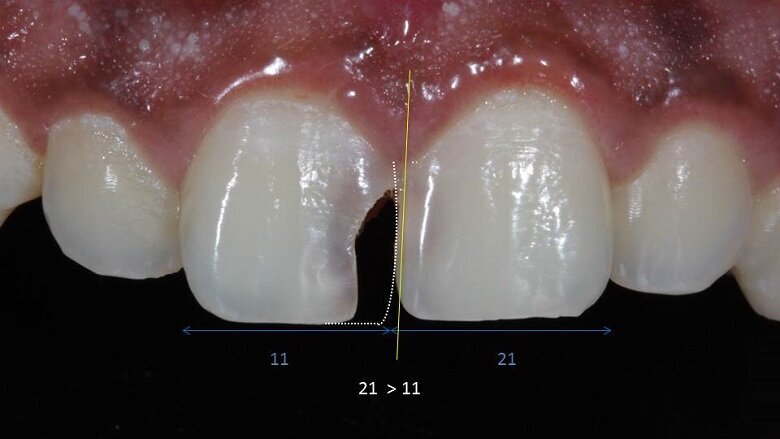

After a digital image was made, it was concluded that if nothing was done to correct the midline shift, the discrepancy in the mesio-distal width would still remain (Fig 3). As bilateral symmetry will not be achieved it would not give an aesthetic and pleasing result. The patient was explained about the clinical situation and he was suggested orthodontic treatment to correct the slight tipping of the 21.

Fig 3: digital image without enameloplasty,

21>11